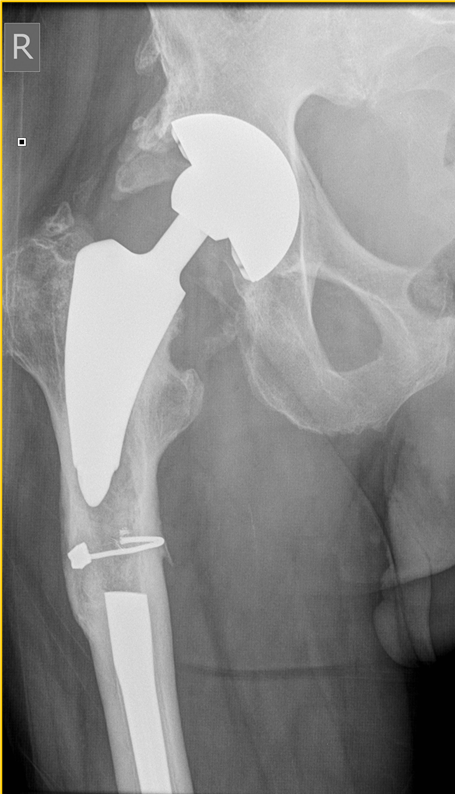

Below are the prostheses with links we commonly use but this is not exhaustive.